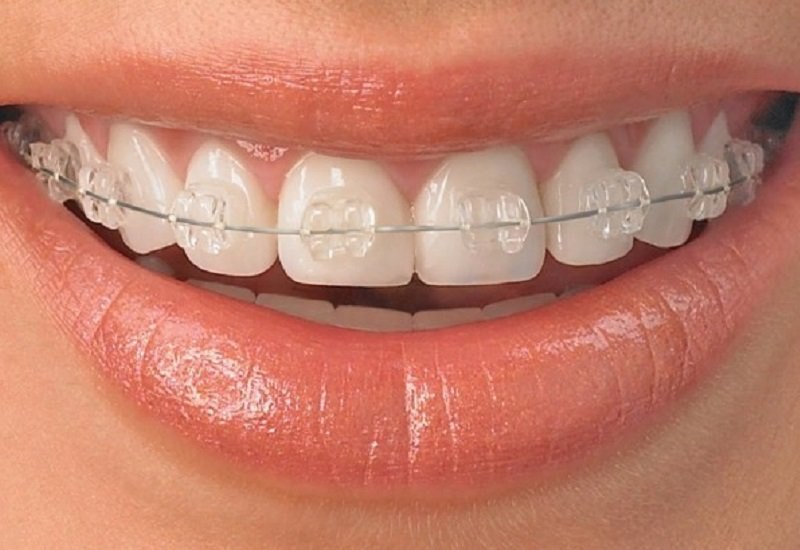

Aparate Dentare Safir

Aparatul dentar safir este un aparat ortodontic fix, diferenta fiind data de materialul din care sunt compusi bracketii. Deoarece nu au compusi metalici, bracketii aparatului dentar din safir pot trece total neobservati datorita transparentei acestora.

Aparatul dentar din safir ofera o eficienta crescuta si rezultate ideale. Bracketii au o rezistenta crescuta si exercita o presiune optima pentru indreptarea dintilor.